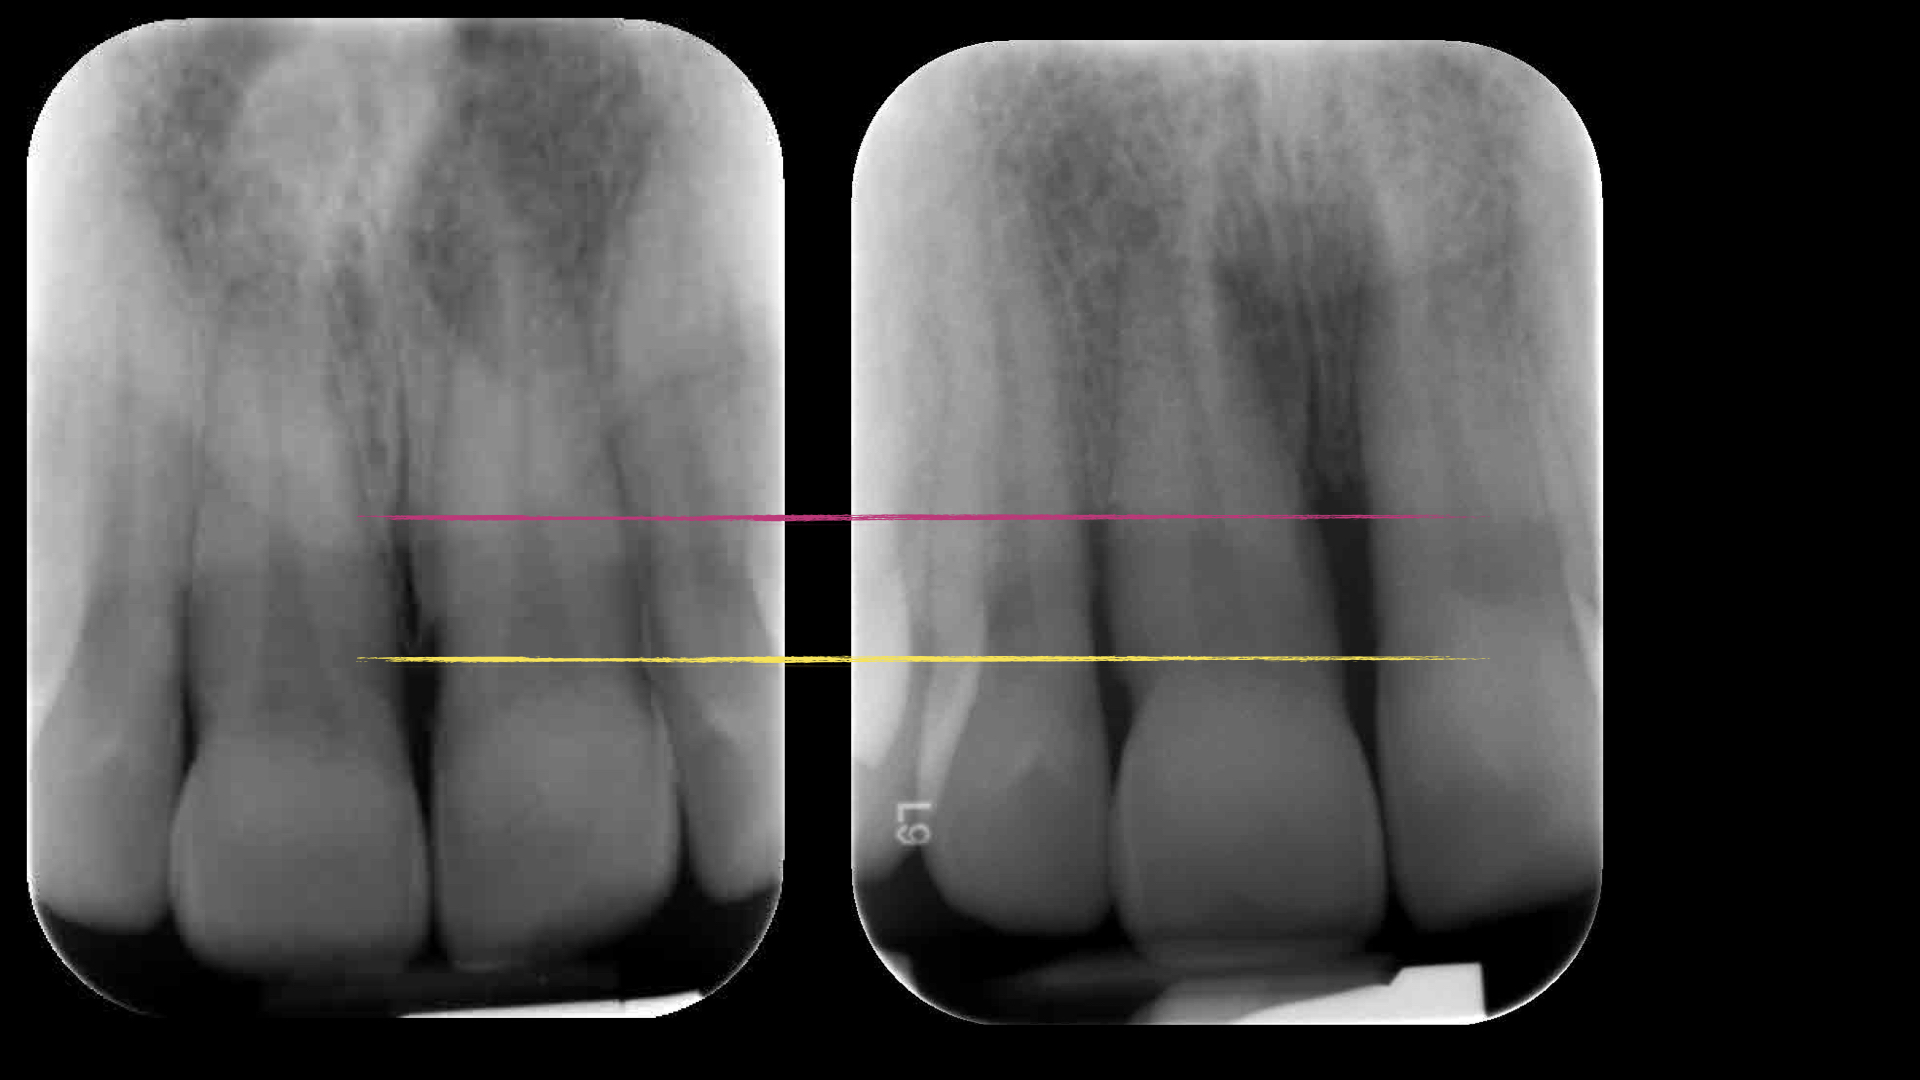

De gele lijn laat de situatie zien in 2012 en de rode lijn 2022.

Als tandvleesontsteking niet op tijd wordt behandeld, kan het overgaan in parodontitis. Dit is een ernstigere vorm waarbij niet alleen het tandvlees, maar ook het kaakbot wordt aangetast. De schade aan het kaakbot die hierdoor ontstaat, is meestal blijvend.

In het begin lijkt het misschien niet ernstig, omdat je geen pijn voelt. Maar stap voor stap kan het tandvlees terugtrekken, het kaakbot afbreken en tanden los gaan staan of uitvallen. Hoe langer je wacht, hoe moeilijker en duurder de behandeling wordt.